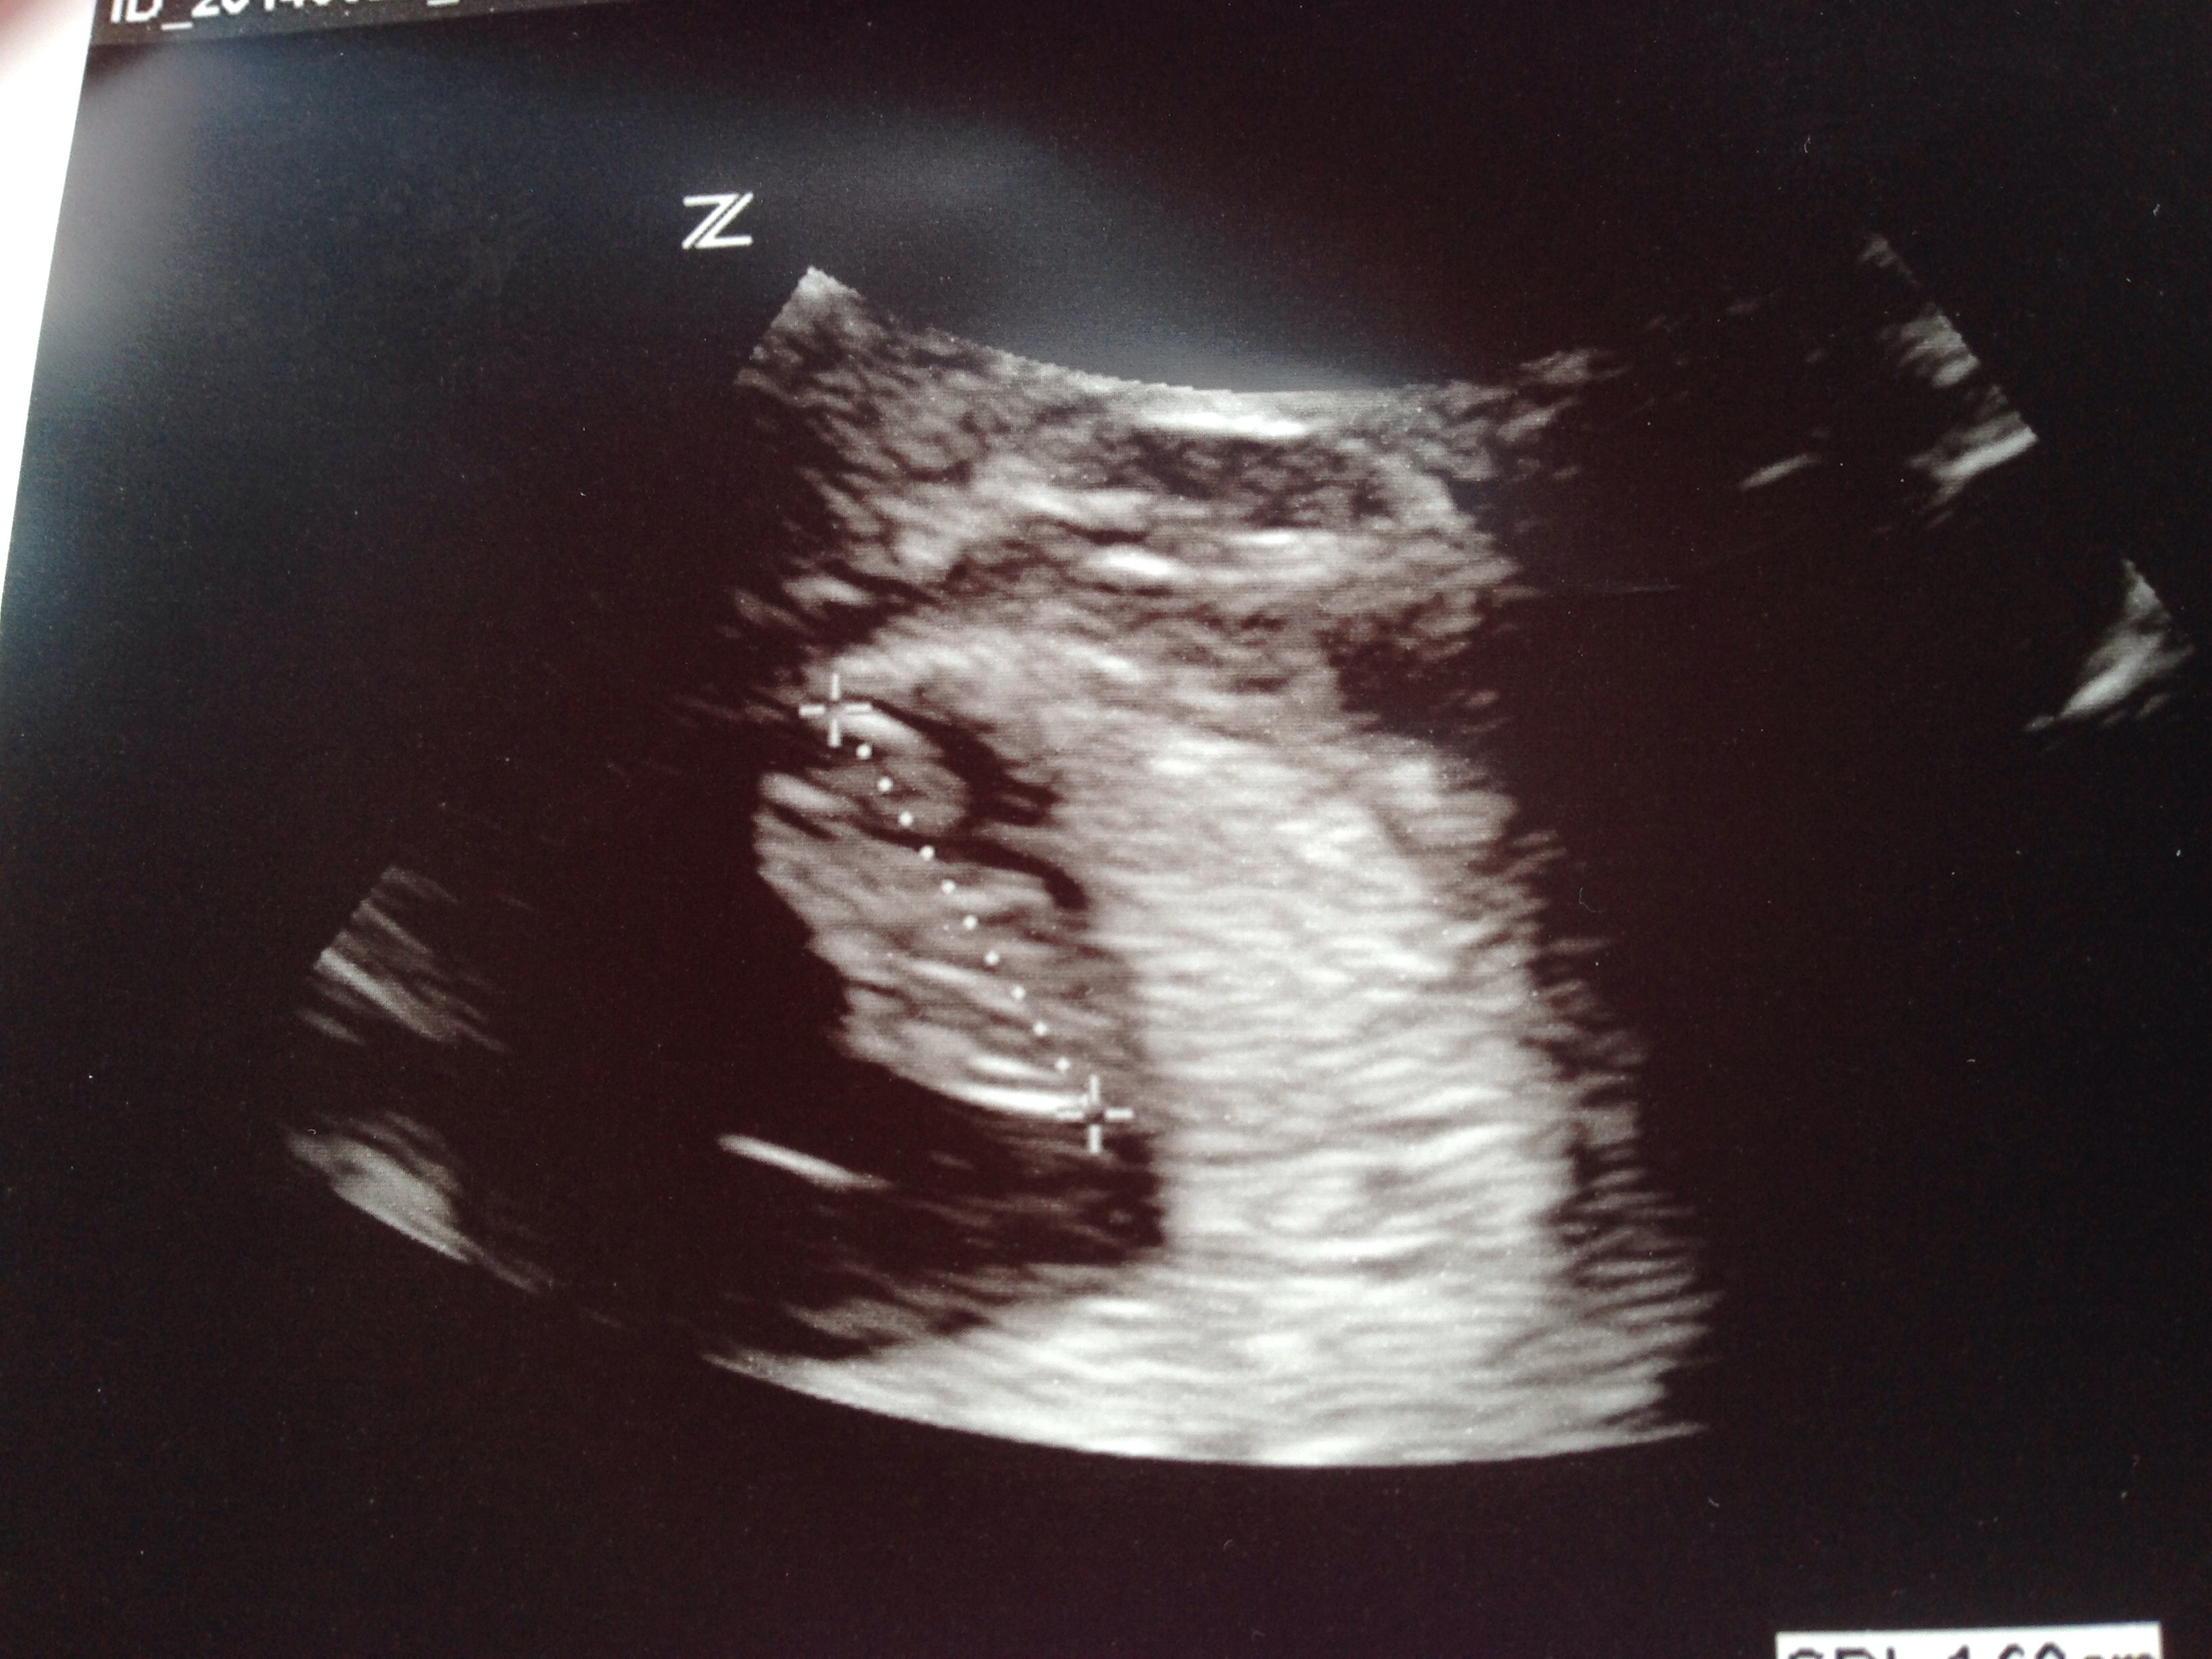

I know this is an extra thread, but how can mamas not be bursting with excitement after the first ultrasound?! I had mine today and got to see little nugget and hear a very strong heartbeat. She got a great angle where you can see the tiny little arm and nub for a hand! It just got real for me! I hope everyone is having a safe and healthy pregnancy! image

• Saw mine on Wed!! I was 8 weeks 1 day. Got to see its little arm and leg!! It was side profile :) heartbeat was 173! Amazing.